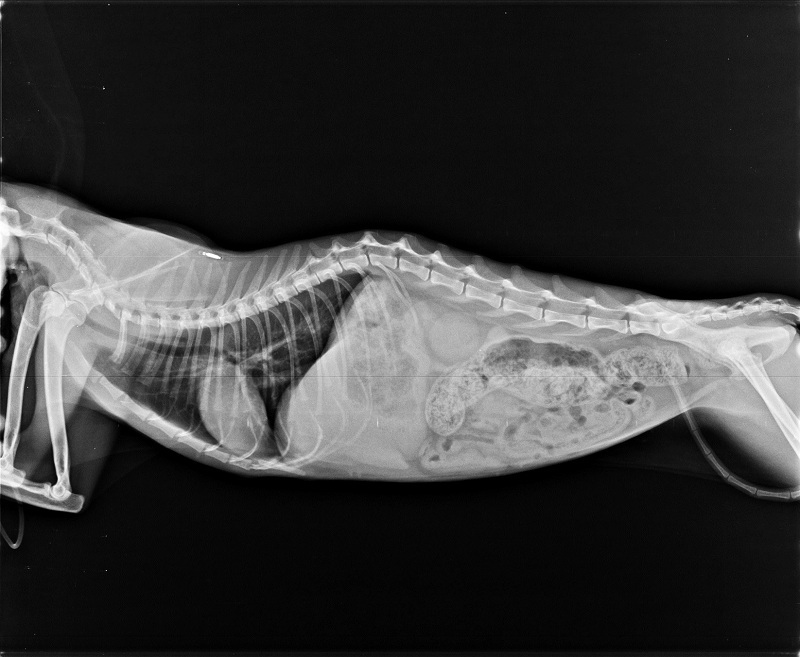

主題: 因脫水耗弱、口腔嚴重發炎,且有鼻膿分泌物的盈盈 申請者姓名: 臺北市支持流浪貓絕育計劃協會 花色: 申請日期: 2017-11-01 12:19:19 申請者部落格: 申請者臉書網址: 所在縣市/合作醫院: 台北市/極光動物醫院 治療費用: 22599元 需求人數: 50人 已結案 (2024-06-01 13:20:53) 報名人員: Nina Chiu(已付款)、Mimi Liu x2(已付款)、Nicole Chen x2(已付款)、yuling(已付款)、Wanting(已付款)、Naommi x2、姿馬麻、Noel6731(已付款)、Amanda Ke(已付款)、阿奇拉 x2(已付款)、Helen Yu(已付款)、張香香、Me I Me I liao x2(已付款)、貓兩拳(已付款)、陳金鳳 x2(已付款)、wgs(已付款)、Arthur Nana(已付款)、Stiff(已付款)、May x4(已付款)、林嘉南(已付款)、Naommi x2(已付款)、Sophia Kuo(已付款)、JUN x2(已付款)、接小力 x2(已付款)、devin(已付款)、陳亮尋 x5(已付款)、塔羅小蘋與客人們(已付款)、小橘子(已付款)、瀅瀅(已付款)、Wi Chen(已付款)、Fatefaye Wu(已付款)、小珍 x2(已付款)、白婷 x2(已付款)、Guan-Yi Li(已付款)、洪凱威 x2(已付款)、 候補人員: 動物病情說明: 8/16~8/30盈盈住院

盈盈因食慾不佳及上呼吸道膿樣分泌物,

於106年8月16日就診。

經醫師檢查發現,盈盈可能歷經全口拔牙,口腔呈現嚴重發炎,並有多數傷口癒合不良之情形

而血液檢查有肝指數上升與貧血之症狀。

合併上呼吸道感染等多數原因,

推斷是造成盈盈無法自行進食、脫水與身體耗弱等之情況。除給予必要點滴維持、抗生素治療與灌食照顧外,

也須同時配合持續性密切的生理數值監測,

因此建議繼續在醫院治療直至穩定出院為止。

動物近況說明: 原先以全口拔為拔乾淨導致持續發炎的盈盈

已經再次接受清除殘留齒根的手術

目前狀況良好